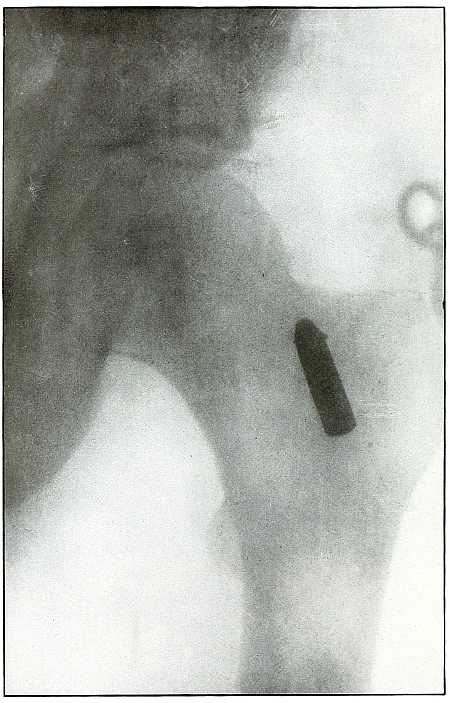

LOWER EXTREMITY.

Plate 47.

[Pg 105]

Rifle—Plate 47.

LOWER EXTREMITY.

Gunshot Wound of the Gluteal Region,

with Lodgment of the Bullet Near the Ischium.

Wound of entrance, over gluteal prominence on a transverse line

through the great trochanter.

Wound of exit, none.

There was no bone injury in this case. The bullet, to have lodged in

the soft parts after relatively slight penetration, must have struck

the body at extreme range when its energy was almost spent in flight,

for its normal outline indicates that it was not retarded by ricochet.

The long axis is almost perpendicular to the plate. As the posterior

pelvis was next to the plate, the fairly dense shadow shows the

projectile was not far from the plate and behind the ischium.

The treatment is conservative; infection in such cases is extremely

rare; and only pain or impaired function after many months of

convalescence justifies operation for removal of the missile.